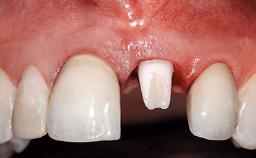

Replacement of an Upper Right Central Incisor with Root Resorption: Ridge Preservation, Delayed Placement of an NC Bone Level Roxolid Implant

A 32-year-old female Caucasian patient with a compromised maxillary right central incisor was referred to us by a general dentist. Her chief complaints were discomfort and mobility of tooth 11 with unsatisfactory esthetics due to discoloration. The patient reported a previous trauma, some years earlier, as the origin of pathology on the afflicted tooth. Anamnesis was negative for any other dental or periodontal pathology in the remaining dentition. The patient did not take any medication and reported to be a light smoker (5–10 cigs/day). She had high esthetic expectations of her treatment. The extraoral examination revealed a high smile line with full exposure of her maxillary teeth and surrounding soft tissue in the area between the second premolars.